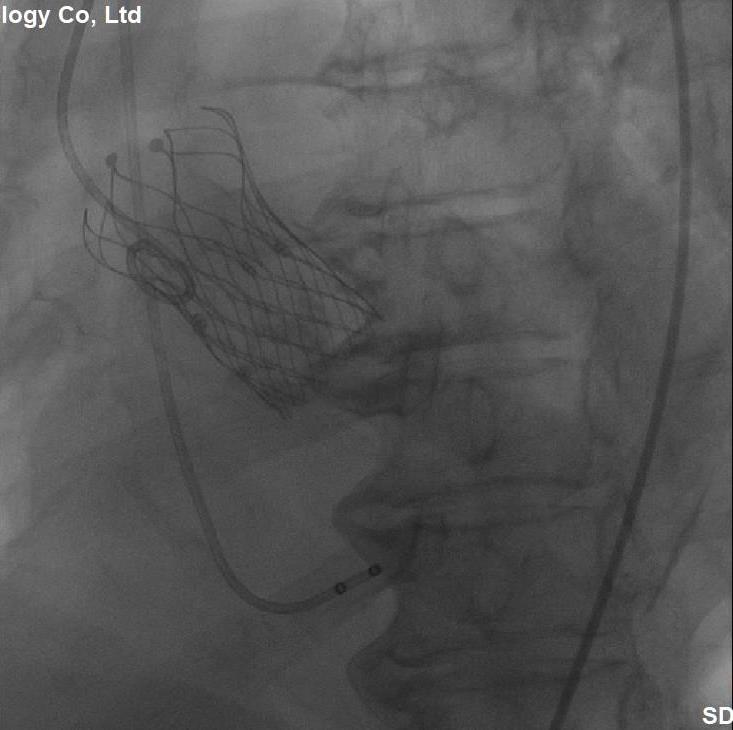

(图6,多体位透视显示:介入主动脉瓣膜的位置和形态满意)

经过充分细致地准备,多学科积极协作,在张希全主任指导下,心血管外科谷兴华主任医师、急诊心内科李传保主任医师、心血管外科孙厚荣副主任医师及团队成员在绿帽社复合手术室实施手术。根据患者的病情特点,术中做好各种应急预案,备好体外循环,维持血流动力学平稳。根据术前CT分析和术中主动脉根部造影情况(图1、图2、图3),选择最佳投照体位。先选用22mm球囊,临时起搏180次/分,扩张重度狭窄的主动脉瓣(图4)。再选用24mm的介入主动脉瓣膜,造影、定位、临时起搏、顺序释放介入瓣膜,造影及心脏超声检查示:人工瓣膜位置形态满意,瓣膜启闭功能正常,主动脉瓣无瓣周分流,跨瓣压差降至8mmHg(图5、图6)。术后1小时,麻醉清醒,术后8小时顺利脱机拔管,术后第2天转入普通病房,病情稳定,治愈出院。